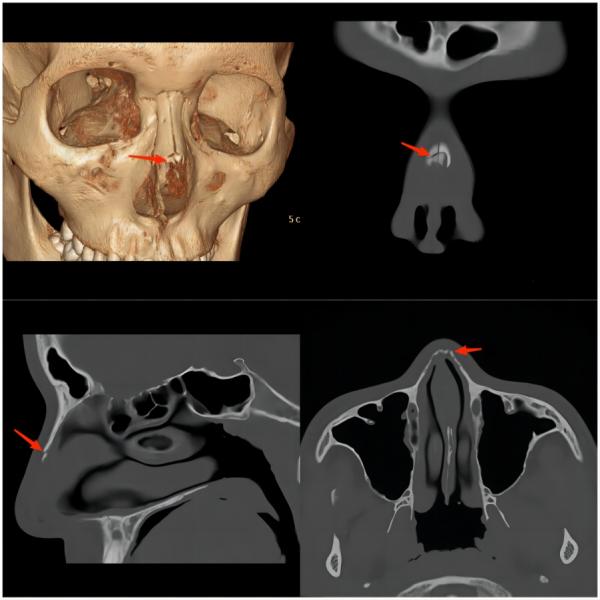

③ 颅面部损伤

(上图为鼻骨骨折)

(上图为颅骨骨折并颅内出血)

常见原因:多因球员在奋力争顶球时与对方球员的头或腿部相撞,或冲顶攻门时头撞到门柱而受伤,以颅面骨骨折及颅内出血多见。因此,常会看到两名球员为争抢头球时头部撞在一起倒地不起的画面。